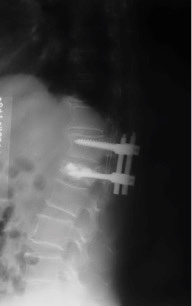

辅助检查:MRI检查示腰1椎体骨质疏松性压缩性骨折。

诊断:腰11椎体骨质疏松性压缩骨折

治疗:因患者椎体压缩骨折明显,椎体后缘骨折不完整,突入椎管,且硬膜囊受压,因此不适合行椎体成形术。给予单节段椎弓根钉固定并椎板切除减压术。骨折椎置钉结合钉道骨水泥加强稳定性。术后随访效果满意。

随访未见内固定松脱,无矫正丢失。